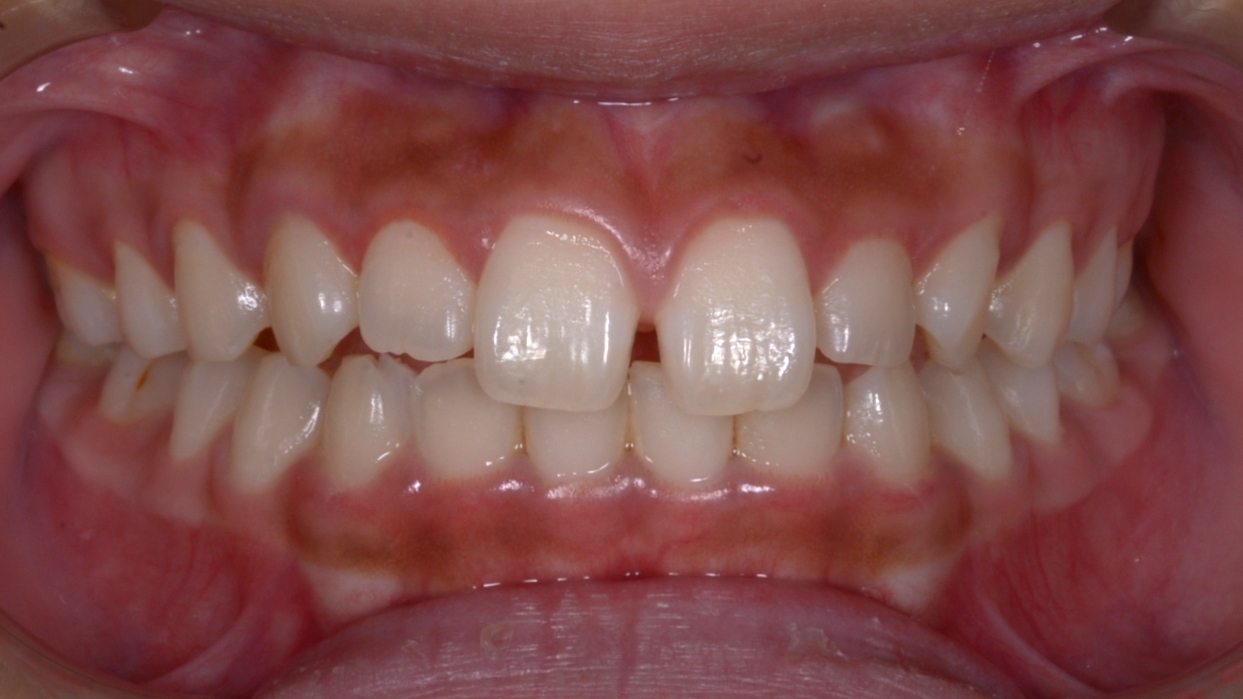

Before

| 主訴 | 右上第1大臼歯が何もしなくても痛い 前歯がすきっぱ 前歯で物が噛みにくい |

| 診断 | 右側アングルクラスⅡ 左側アングルクラスⅠ 正中離開 前歯オープンバイト |